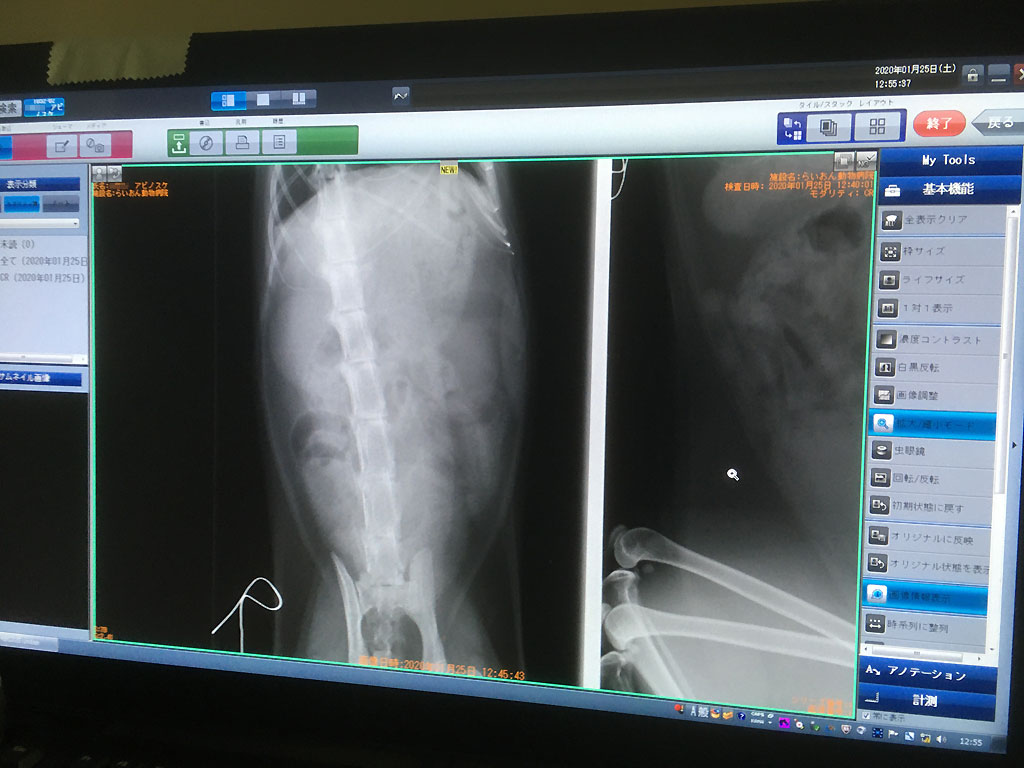

そして、念の為、石が詰まってないかレントゲンを勧められたので、こちらからもして欲しかった位なので、すぐにお願いしました。

まずは横からのレントゲン。

レントゲンを見てもいつもよく分からないのですが、先生のご説明によると、取り敢えず、石は詰まってないとの事、そして、尿も膀胱にパンパンに溜まっている程ではないとの事。

とにかく、石が詰まって尿が出ず、急性の腎不全に陥って死んでしまうという事はなさそうだったので、本当に安心したぞ、アビのすけ君。